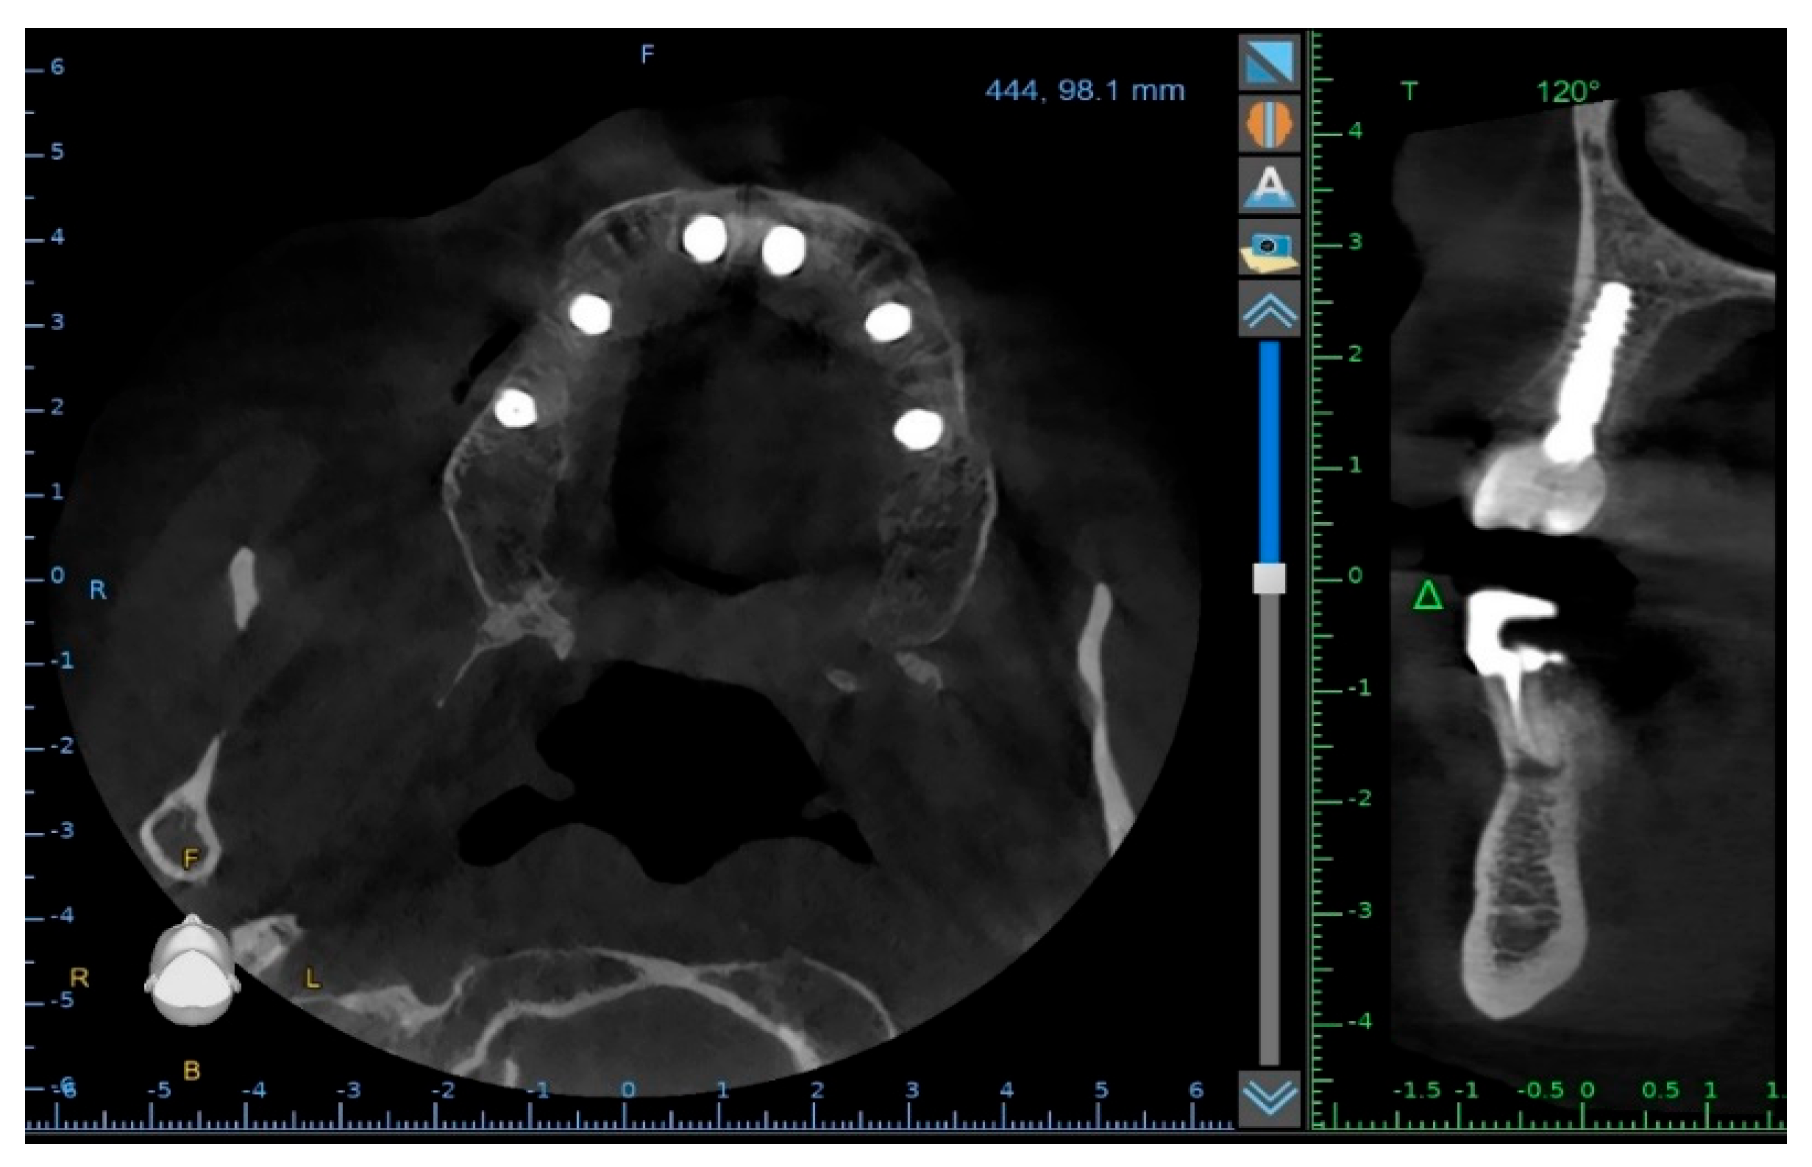

To supplement the clinical findings, a cone beam computed tomography (CBCT) scan was obtained (Figure 1) and evaluated. The implants existing in the maxilla demonstrated proper surrounding bone architecture. The compromised status of the remaining teeth was confirmed. In addition, the available bone conditions in the regions of teeth 14 and 24 were assessed to be adequate for future implant placement, particularly in the context of immediate implant insertion. This is in accordance with the literature emphasising that sufficient bone volume, labial plate integrity, and socket morphology, are critical prerequisites for successful immediate implant placement [7,8,9].

To verify the implant positions and the accuracy of the prosthetic fit, a control CBCT scan was obtained after the delivery of the early provisional restoration. Radiological evaluation confirmed stable positioning of the implants and correct seating of the prosthesis (Figure 11 and Figure 12).

Figure 1. Preoperative panoramic reconstruction from CBCT, showing the initial condition of the existing tooth- and implant-supported restorations in the maxilla and mandible, as well as the visualisation of two planned implants in positions 14 and 24.

Figure 11. Control CBCT scan obtained after the delivery of the early full-arch provisional restoration.

Figure 12. Control CBCT scan obtained after the delivery of the early full-arch provisional restoration.